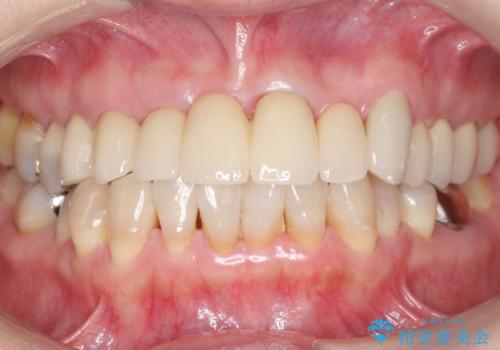

歯列不正と歯周病 総合歯科治療による全顎治療

担当医 藤巻太一朗

[前歯の変色] 前歯の見た目を改善したい

![[前歯の変色] 前歯の見た目を改善したいの症例 治療後](https://seimitsushinbi.jp/wp/wp-content/uploads/2021/05/1f01d9f0751d14a2f5d20ed7475c6e38-500x350.jpg?v=1622180216)